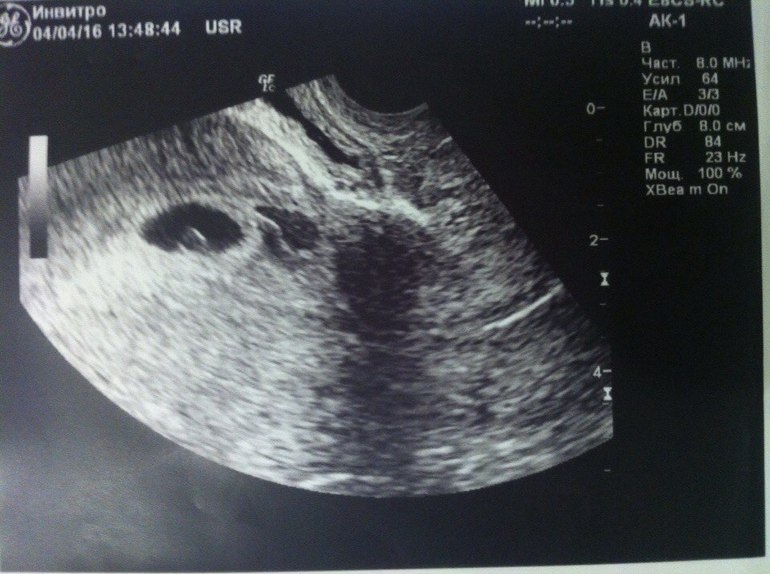

У нас тоже была гематома на раннем сроке, но это УЗИ в 5 и 4 недельки. Вообще я подумала,что гематома -это второй не прижившийся эмбрион. Уж очень они по форме и размерам близки

Слева эмбрион, справа гематома,с заостренным концом